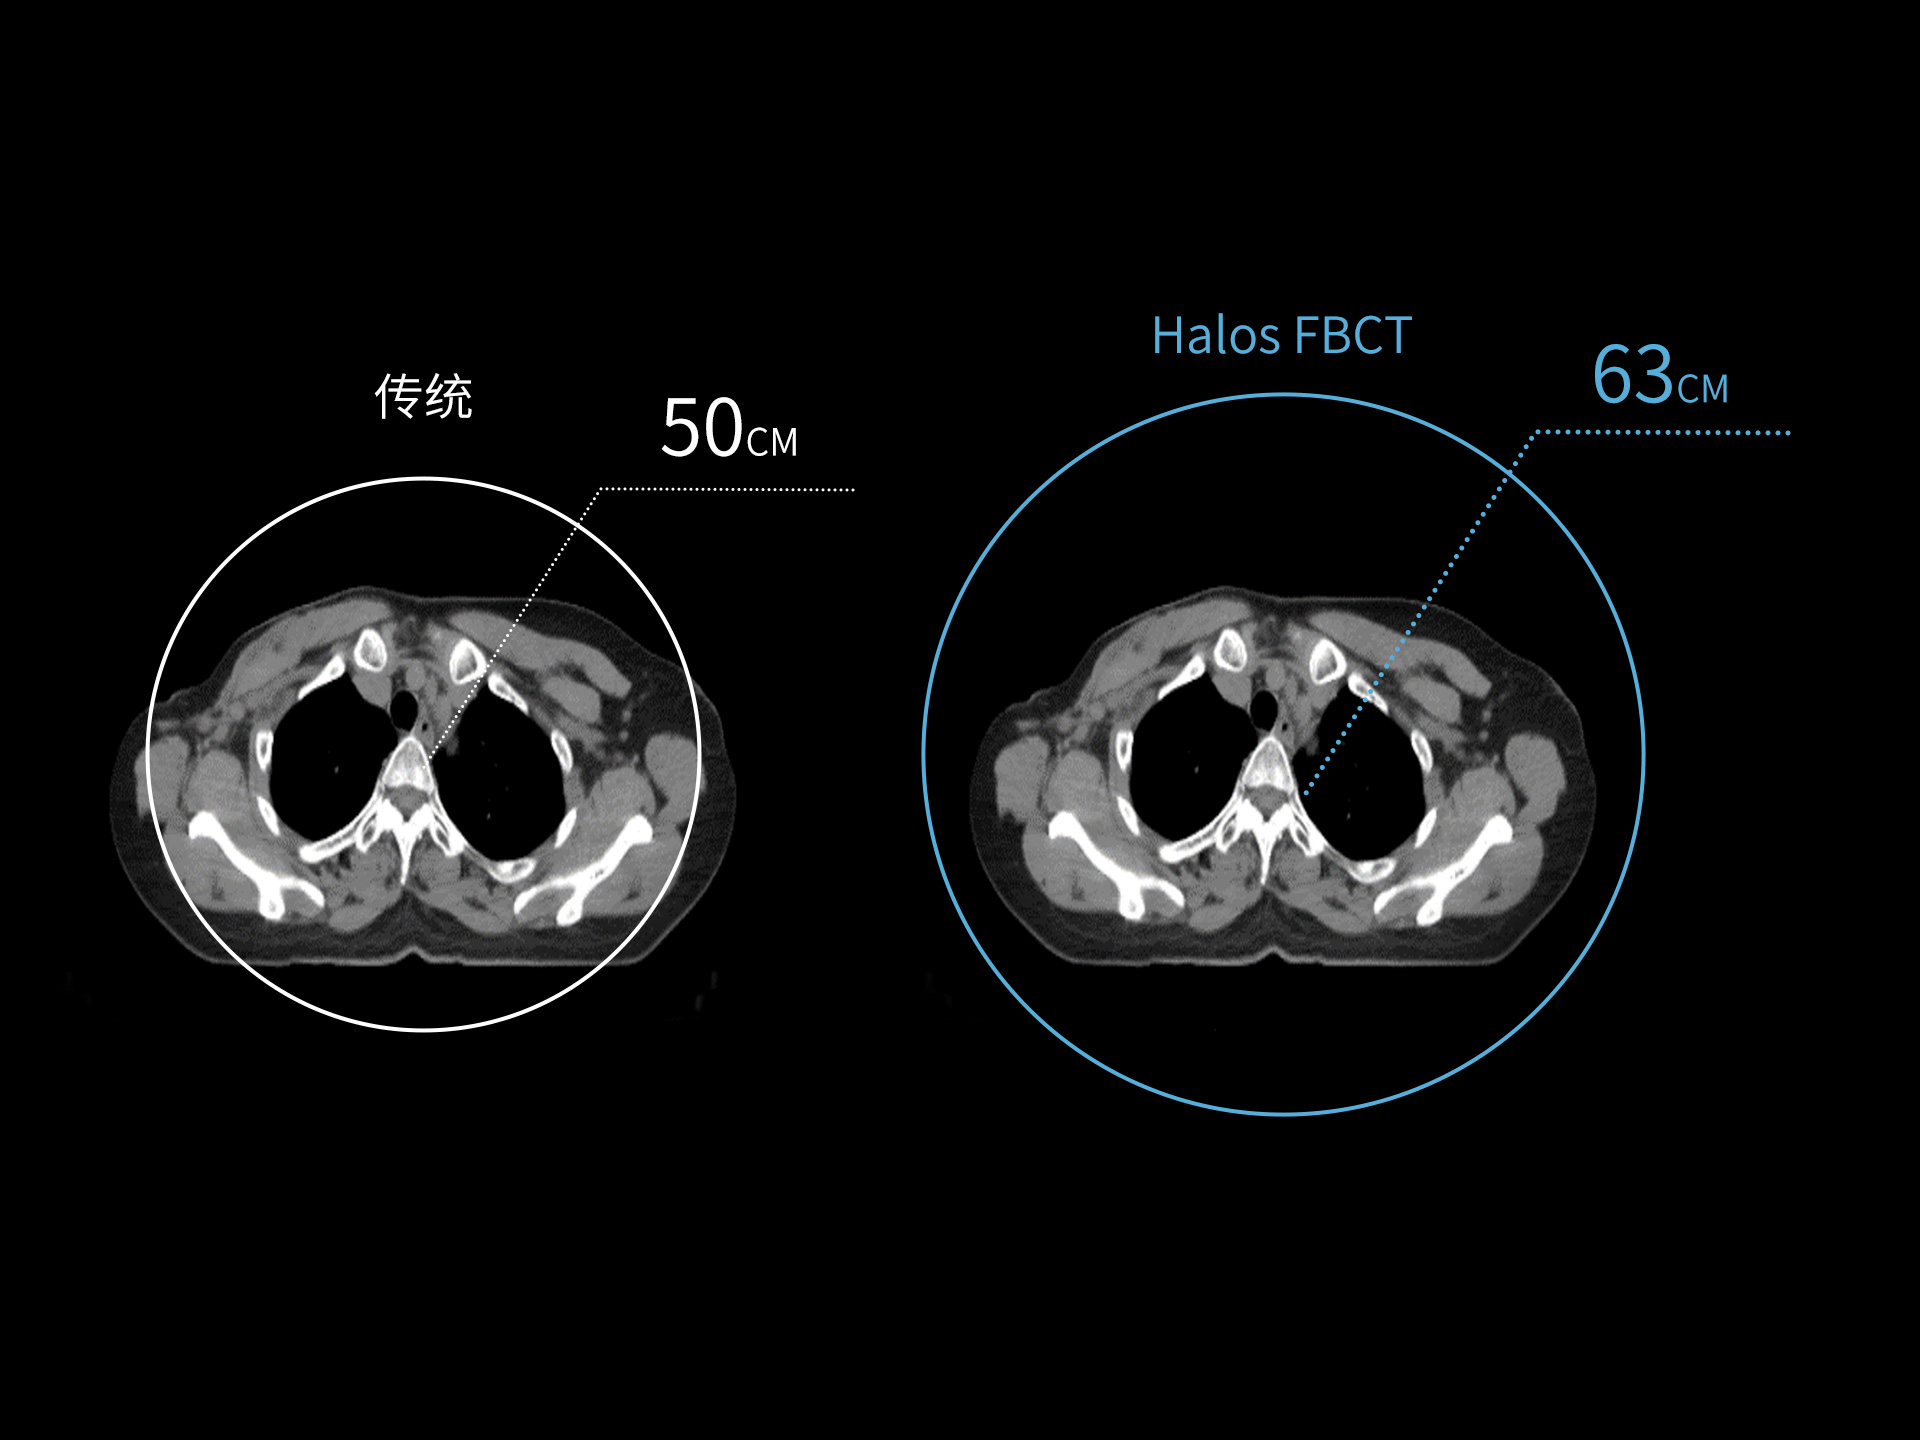

标准视野 63cm,避免扫描信息缺失

全景视野